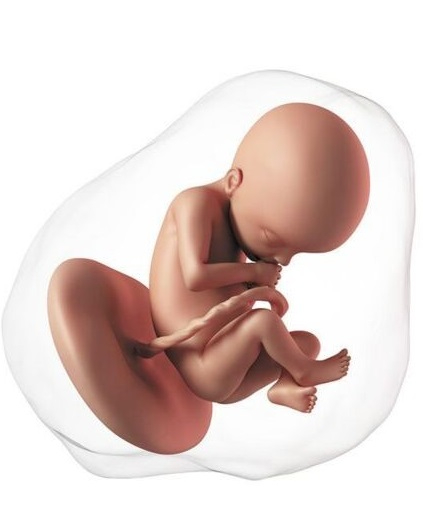

El bebé ahora mide entre 40 a 60 mm. Aunque la cabeza aún es muy grande en relación con el cuerpo, este se va alargando y se va diferenciando la zona de la barbilla y el cuello. El feto empieza a deglutir (tragar) de forma regular y a pasar líquido al sistema digestivo, que está en pleno desarrollo. Excepto el cerebro, la mayoría de órganos están formados "por fuera". Esto quiere decir que su aspecto ya es casi el mismo que tendrán el resto de su vida, pero en su interior todavía sucederán cambios hasta que estén preparados para funcionar fuera de mamá. Los riñones han iniciado ya la producción propia de orina. Esto es necesario para garantizar una adecuada cantidad de líquido amniótico puesto que más adelante la orina será su componente más importante. El líquido cumple un papel fundamental para el bebé; garantiza que el feto está protegido en caso de un golpe accidental a la madre, ayuda a mantener una temperatura estable, impide que el cordón umbilical se comprima, permite el desarrollo pulmonar y del sistema gastrointestinal.

Cada vez se parece más a un bebé. Mide aproximadamente 11 a 12 cm y pesa unos 80 gramos. La proporción cabeza-cuerpo se acerca más a la que tendrá después del nacimiento, las orejas y los ojos están casi en su posición final. Los brazos y las piernas se alargan. La conexión entre el cerebro y los músculos madura, el bebé empieza a realizar movimientos coordinados. Puede mover los ojos, tragar, abrir y cerrar las manos, flexionar las extremidades y también puede coger con las manos los pies e incluso el cordón umbilical. La función del riñón está completa, ahora la orina será el principal componente del líquido amniótico. Un nivel normal de líquido indica que el feto está orinando de manera adecuada.